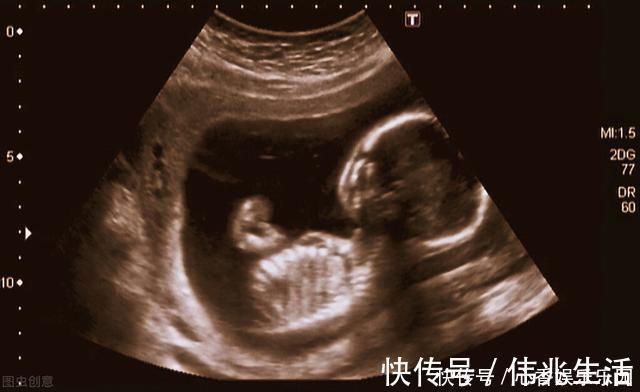

但是在做B超时,他们看到了胎儿,他已有成形的手指和脚趾,正在吮吸着自己的手指头,那个样子看起来很幸福。这“幸福的胎儿”让父亲心痛,虽然还在妈妈的肚子里,可是他们非常爱他。他们决定要救这个孩子。于是两人走遍全国,四处求医,最后他们选择了一种处于实验阶段的手术,叫宫内手术,就是在动态实时超声的引导下,给胎儿做手术。这种手术的危险不言而喻,但是克鲁斯·兰德夫妇仍然选择了它!